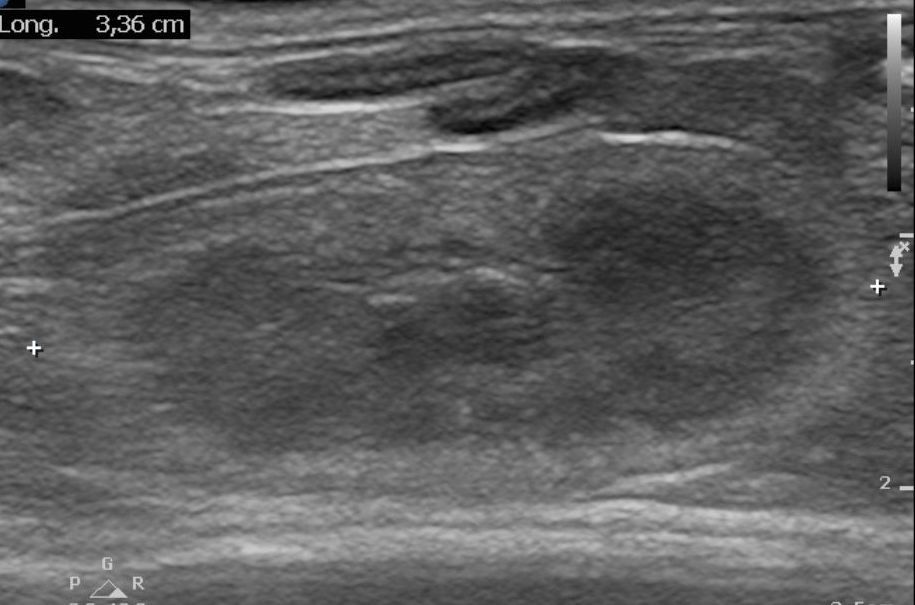

Lorsque les glandes surrénales sont fortement stimulées, elles deviennent progressivement hyperplasiques puis tumorales (tumeur bénigne puis maligne). Le diagnostic peut être établi par échographie, réalisée par un vétérinaire expérimenté avec les furets, et par une prise de sang (dosage des hormones en question). Suivant l'extension et la présence ou non d'embole vasculaire, il est recommandé de poser un implant hormonal ou de réaliser une surrénalectomie. Cette chirurgie est particulièrement risquée à cause de la proximité des glandes surrénales avec l'aorte, un vaisseau sanguin vital pour l'organisme. Il peut être utile d'utiliser des outils de microchirurgie ainsi que du matériel de pointe tel qu'une caméra endoscopique per-opératoire Vitum pour maximiser la réussite de la chirurgie.

Le diagnostic se fait par prise de sang et par échographie, réalisée par un vétérinaire expérimenté. Parfois, un traitement doit être administré en urgence, car les crises d'hypoglycémie peuvent être mortelles. Une hospitalisation est nécessaire en cas de crises convulsives. Les premières phases du traitement sont médicales mais une chirurgie (pancréatectomie) peut être recommandée dans certaines formes d'insulinome. Nous utilisons pour ce faire la technologie Ligasure pour minimiser le temps opératoire et les risques associés à l'opération.

Les furets présentent des maladies rénales, en particulier lorsqu'ils sont âgés de plus de 5 ans. Des prises de sang et des analyses d'urine régulières sont recommandées pour déceler d'éventuelle anomalie le plus précocement possible. Les furets sont également très sujets aux anomalies rénales congénitales. Les furets souffrant de maladie rénale boivent souvent beaucoup, maigrissent et peuvent apparaitre abattu. Une échographie abdominale est essentielle pour le diagnostic de ces maladies. Le traitement fait appel à des ajustements alimentaires, parfois une hospitalisation et dans certains cas une intervention chirurgicale.